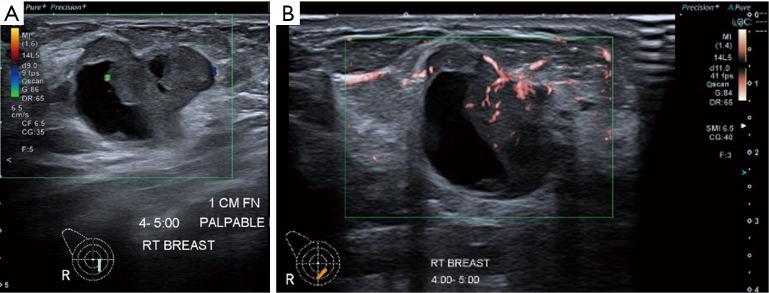

Several new ultrasound tools have been developed to further evaluate breast lesions detected on B-mode ultrasound. Strain elastography (SRE) was developed to assess the likelihood of malignancy of lesions based on their stiffness. This has been incorporated into the latest edition of the American College of Radiology (ACR) Breast Imaging Reporting and Data System (BI-RADS) lexicon and atlas. However, no agreed cut-off stiffness values have been established to distinguish benign from malignant lesions making the translation into routine clinical practice difficult. Superb microvascular imaging (SMI) was developed to better evaluate the vascularity within sonographic lesions and assess their likelihood of malignancy. However, there is also no agreed cut-off value for vascular index (VI) to distinguish between benign and malignant lesions. MicroPure was developed to better visualize and evaluate calcifications seen on ultrasound. Its effective use in breast screening and evaluating the calcifications detected for likelihood of malignancy have not been established. This article describes the original intended uses of these applications and reviews the studies evaluating them, showing the varying success of the translation of these tools into routine clinical practice. Also described are some other uses of these tools for which they were not originally intended. This illustrates the importance of being perceptive to alternative uses of imaging tools in their translation from bench to bedside.

已经开发了几种新的超声工具,以进一步评估在B型超声检查中发现的乳腺病变。应变弹性成像(SRE)是为了根据病变的硬度评估其恶性可能性而开发的。这已被纳入美国放射学会(ACR)乳腺影像报告和数据系统(BI-RADS)词汇表和图谱的最新版本。然而,尚未确定用于区分良性和恶性病变的一致的硬度临界值,这使得其难以转化为常规临床实践。超级微血管成像(SMI)是为了更好地评估超声病变内的血管情况并评估其恶性可能性而开发的。然而,对于区分良性和恶性病变的血管指数(VI)也没有一致的临界值。MicroPure是为了更好地显示和评估超声所见的钙化而开发的。其在乳腺筛查中的有效应用以及评估检测到的钙化的恶性可能性尚未得到证实。本文描述了这些应用的最初预期用途,并回顾了评估它们的研究,展示了这些工具转化为常规临床实践的不同成功程度。还描述了这些工具的一些并非最初预期的其他用途。这说明了在成像工具从实验室到临床的转化过程中,敏锐地感知其替代用途的重要性。